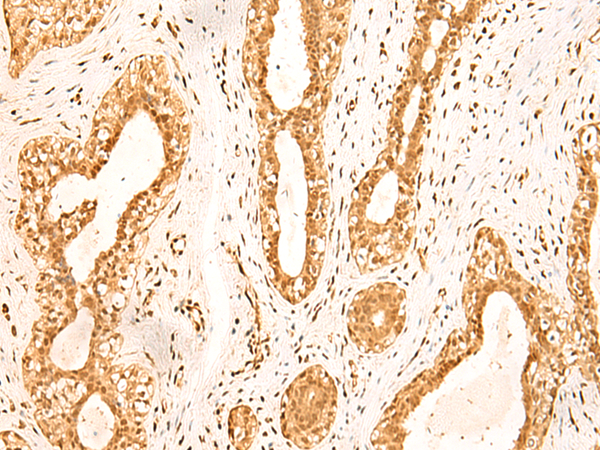

ELISA, IHC |

IHC positive control: |

Human breast cancer and Human ovarian cancer |

IHC Recommend dilution: |

50-300 |